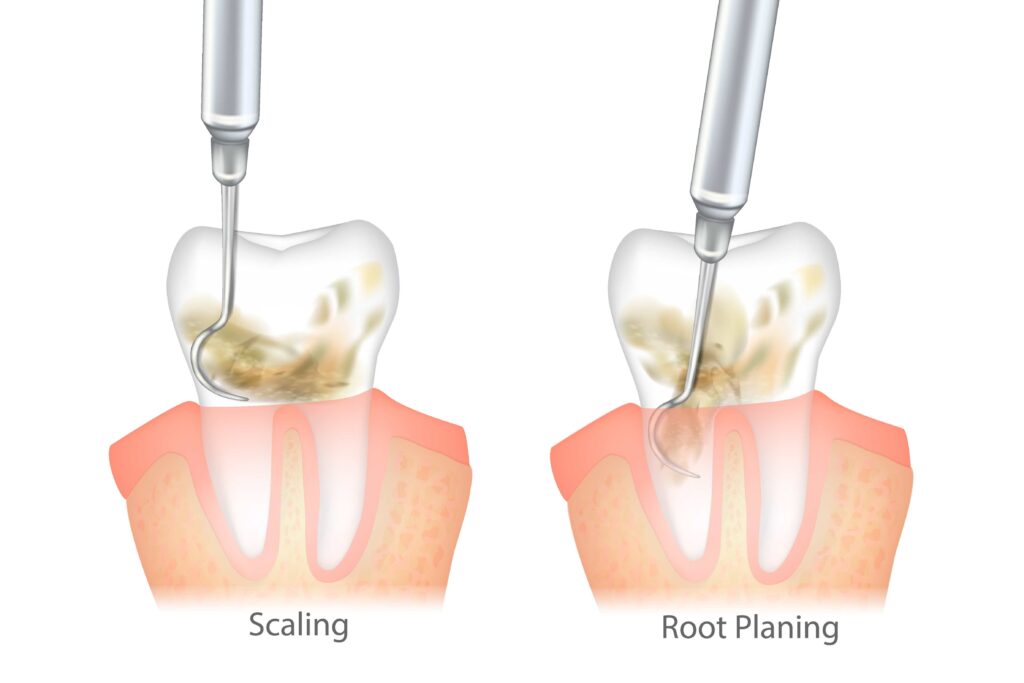

Gingivitis, the earliest form of gum disease, can often be reversed by improving your at-home dental hygiene routine or scheduling more consistent checkups with your oral healthcare provider. However, it’s notoriously hard to catch in the beginning stages, so it frequently progresses to more advanced periodontal problems.

As your condition worsens, your connective tissues eventually retract from your enamel to try to escape the infection. They don’t grow back independently, but your periodontist can provide a gum graft to preserve your oral health. Continue reading to learn more about 3 procedures they might suggest to improve your condition!